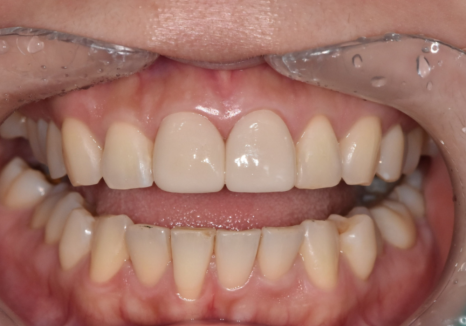

이 환자분은 예전에

앞니 사이가 벌어져 보여서

레진으로 공간을 메우는 치료를 받으셨습니다.

그런데 1년 정도 지나고 나니

레진을 붙였던 부위가

갈색으로 비쳐 보이기 시작했다고 하셨어요.

먼저 방사선 사진으로 확인해보니

다행히 2차 충치가 뚜렷하게 보이거나,

문제가 있어 보이지 않았습니다.

이럴 때는

새로 레진을 하기 보다는

눈에 띄는 겉면만

폴리싱(연마, 다듬기)으로 정리해도

변색된 부분을 충분히 지울 수가 있습니다.